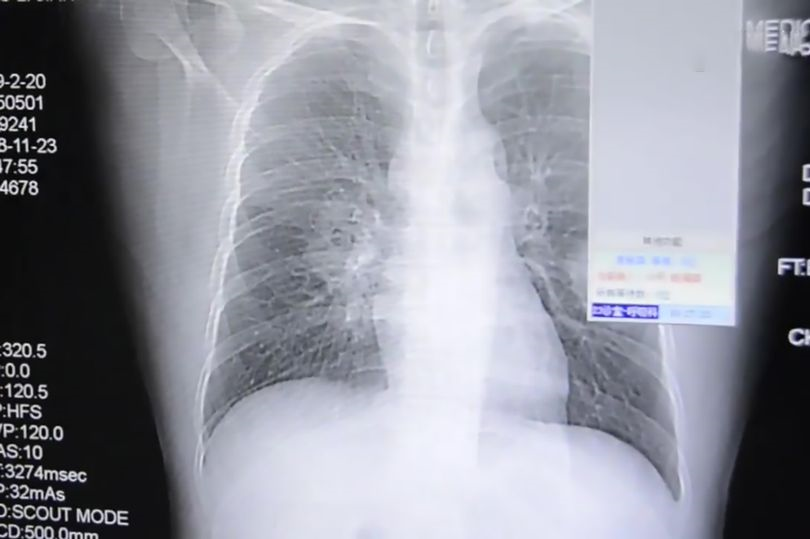

Sinar X yang menunjukkan jangkitan kulat pada paru-paru lelaki terbabit. - AsiaWire

Lelaki itu dimasukkan ke hospital sebagai kes kecemasan dan sinar X yang dilakukan mengesahkan bahawa dia mengalami jangkitan paru-paru yang teruk.